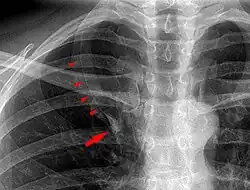

De lobus venae azygos als anatomische variant van een normale long wordt meestal als toevalsbevinding ontdekt bij radiologisch onderzoek. Op longfoto's is de fissura venae azygos namelijk als een gebogen witte lijn zichtbaar in het mediale bovenveld van de rechterlong.[1]

Het verschijnen van de sikkelvormige fissura venae azygos op röntgenfoto's van de borst werd voor het eerst beschreven door Wessler en Jaches in 1923.[2] In 1927 werd reeds gesuggereerd dat de op röntgenfoto's zichtbare schaduw een extra longkwab voorstelde, maar bewijs door middel van obductie kon toen vooralsnog niet worden geleverd.[3] De extra longkwab bleek bij nader onderzoek reeds in 1778 door Heinrich August Wrisberg te zijn beschreven en wordt derhalve soms aangemerkt als lobus Wrisbergi. Na 1927 verschenen er diverse publicaties die de röntgenologische bevinding beschreven, in enkele gevallen met bevestiging door middel van autopsie. Tevens werd beschreven dat een vergrote thymus of een achter het borstbeen gelegen schildklier de anatomische anomalie konden simuleren op röntgenfoto's.[1]